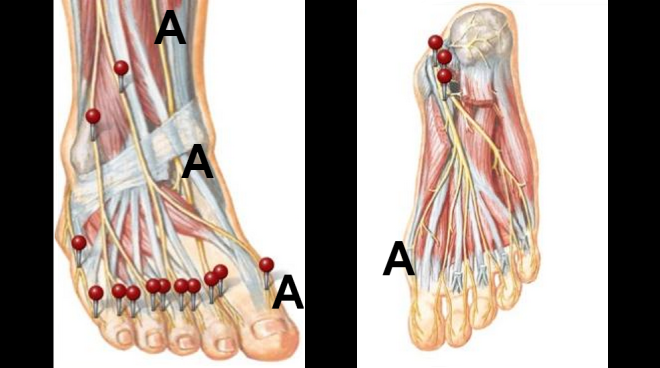

Pain in the big toe when due to peripheral neuropathy, may only be located on the inside part of the big toe, (letter A) and going up the inside portion of your leg towards your knee. (letter A) Dermatome chart courtesy of Grant’s Atlas of Anatomy. Order Grant Atlas of Anatomy at Barnes & Noble